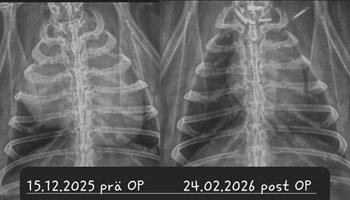

Bei einer Thymom- oder Lymphom-OP handelt sich um einen schwerwiegenden Eingriff, bei dem der Brustkorb des Patienten eröffnet wird und der Tumor möglichst vollständig entfernt werden muss, ohne dabei das benachbarte Herz zu schädigen. Die OP wird nur von wenigen Chirurgen angeboten. Ein Spezialist, der regelmäßig auch Patienten aus Deutschland operiert, ist Dr. Florent Modesto in Brüssel.

Sofern davon auszugehen ist, dass das Kaninchen den Eingriff übersteht und der Tumor sich vollständig entfernen lässt, ist die OP zwar die kostspieligste, aber vermutlich auch die Option mit der besten Prognose

Leider ist trotz allem damit zu rechnen, dass Zellreste des Tumors zurückbleiben und nach einiger Zeit nachwachsen. Je nach Tumor-Art ist dies allerdings mitunter erst nach 3-5 Jahren der Fall - womit das Kaninchen sehr viel Lebenszeit gewonnen hat; hinzu kommt die verbesserte Lebensqualität, nachdem die Masse aus dem Brustkorb entfernt wurde und langfristig auch keine Medikamente gegeben werden müssen.

Nach der chirurgischen Entfernung des Tumors bleibt der Patient stationär am Schmerzmittel-Dauertropf, bis er stabil bei gutem Allgemeinbefinden ist.

Um eine komplikationslose Heilung der Nähte und des Brustbeins zu gewährleisten, muss das Kaninchen in den ersten 4 Wochen nach der OP in einem kleinen Krankenbereich (Zimmerkäfig oder kleines Gehege) untergebracht werden, da es keinesfalls rennen, springen oder übermäßig hoppeln darf.